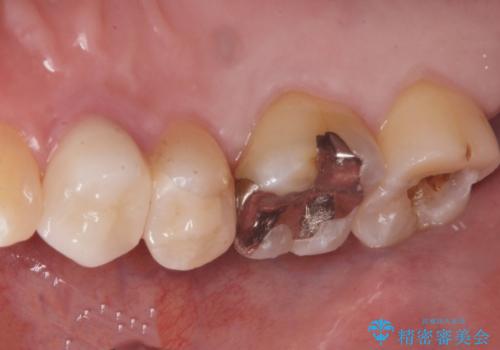

奥の歯に穴が空いている

- 奥の歯に穴が空いているとの事で来院。

拡大鏡下で虫歯を全て除去しゴールドインレーにて治療しました。